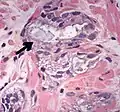

- Collagenous micronodules[4]

- Glomerulations,[4] epithelial proliferations into one or more gland lumina, typically a cribriform tuft with a single attachment to the gland wall.[18]

- Perineural invasion.[4] It should be circumferential[18][notes 5]

- Angiolymphatic invasion[4]

- Extraprostatic extension [4]

- Glomerulation.